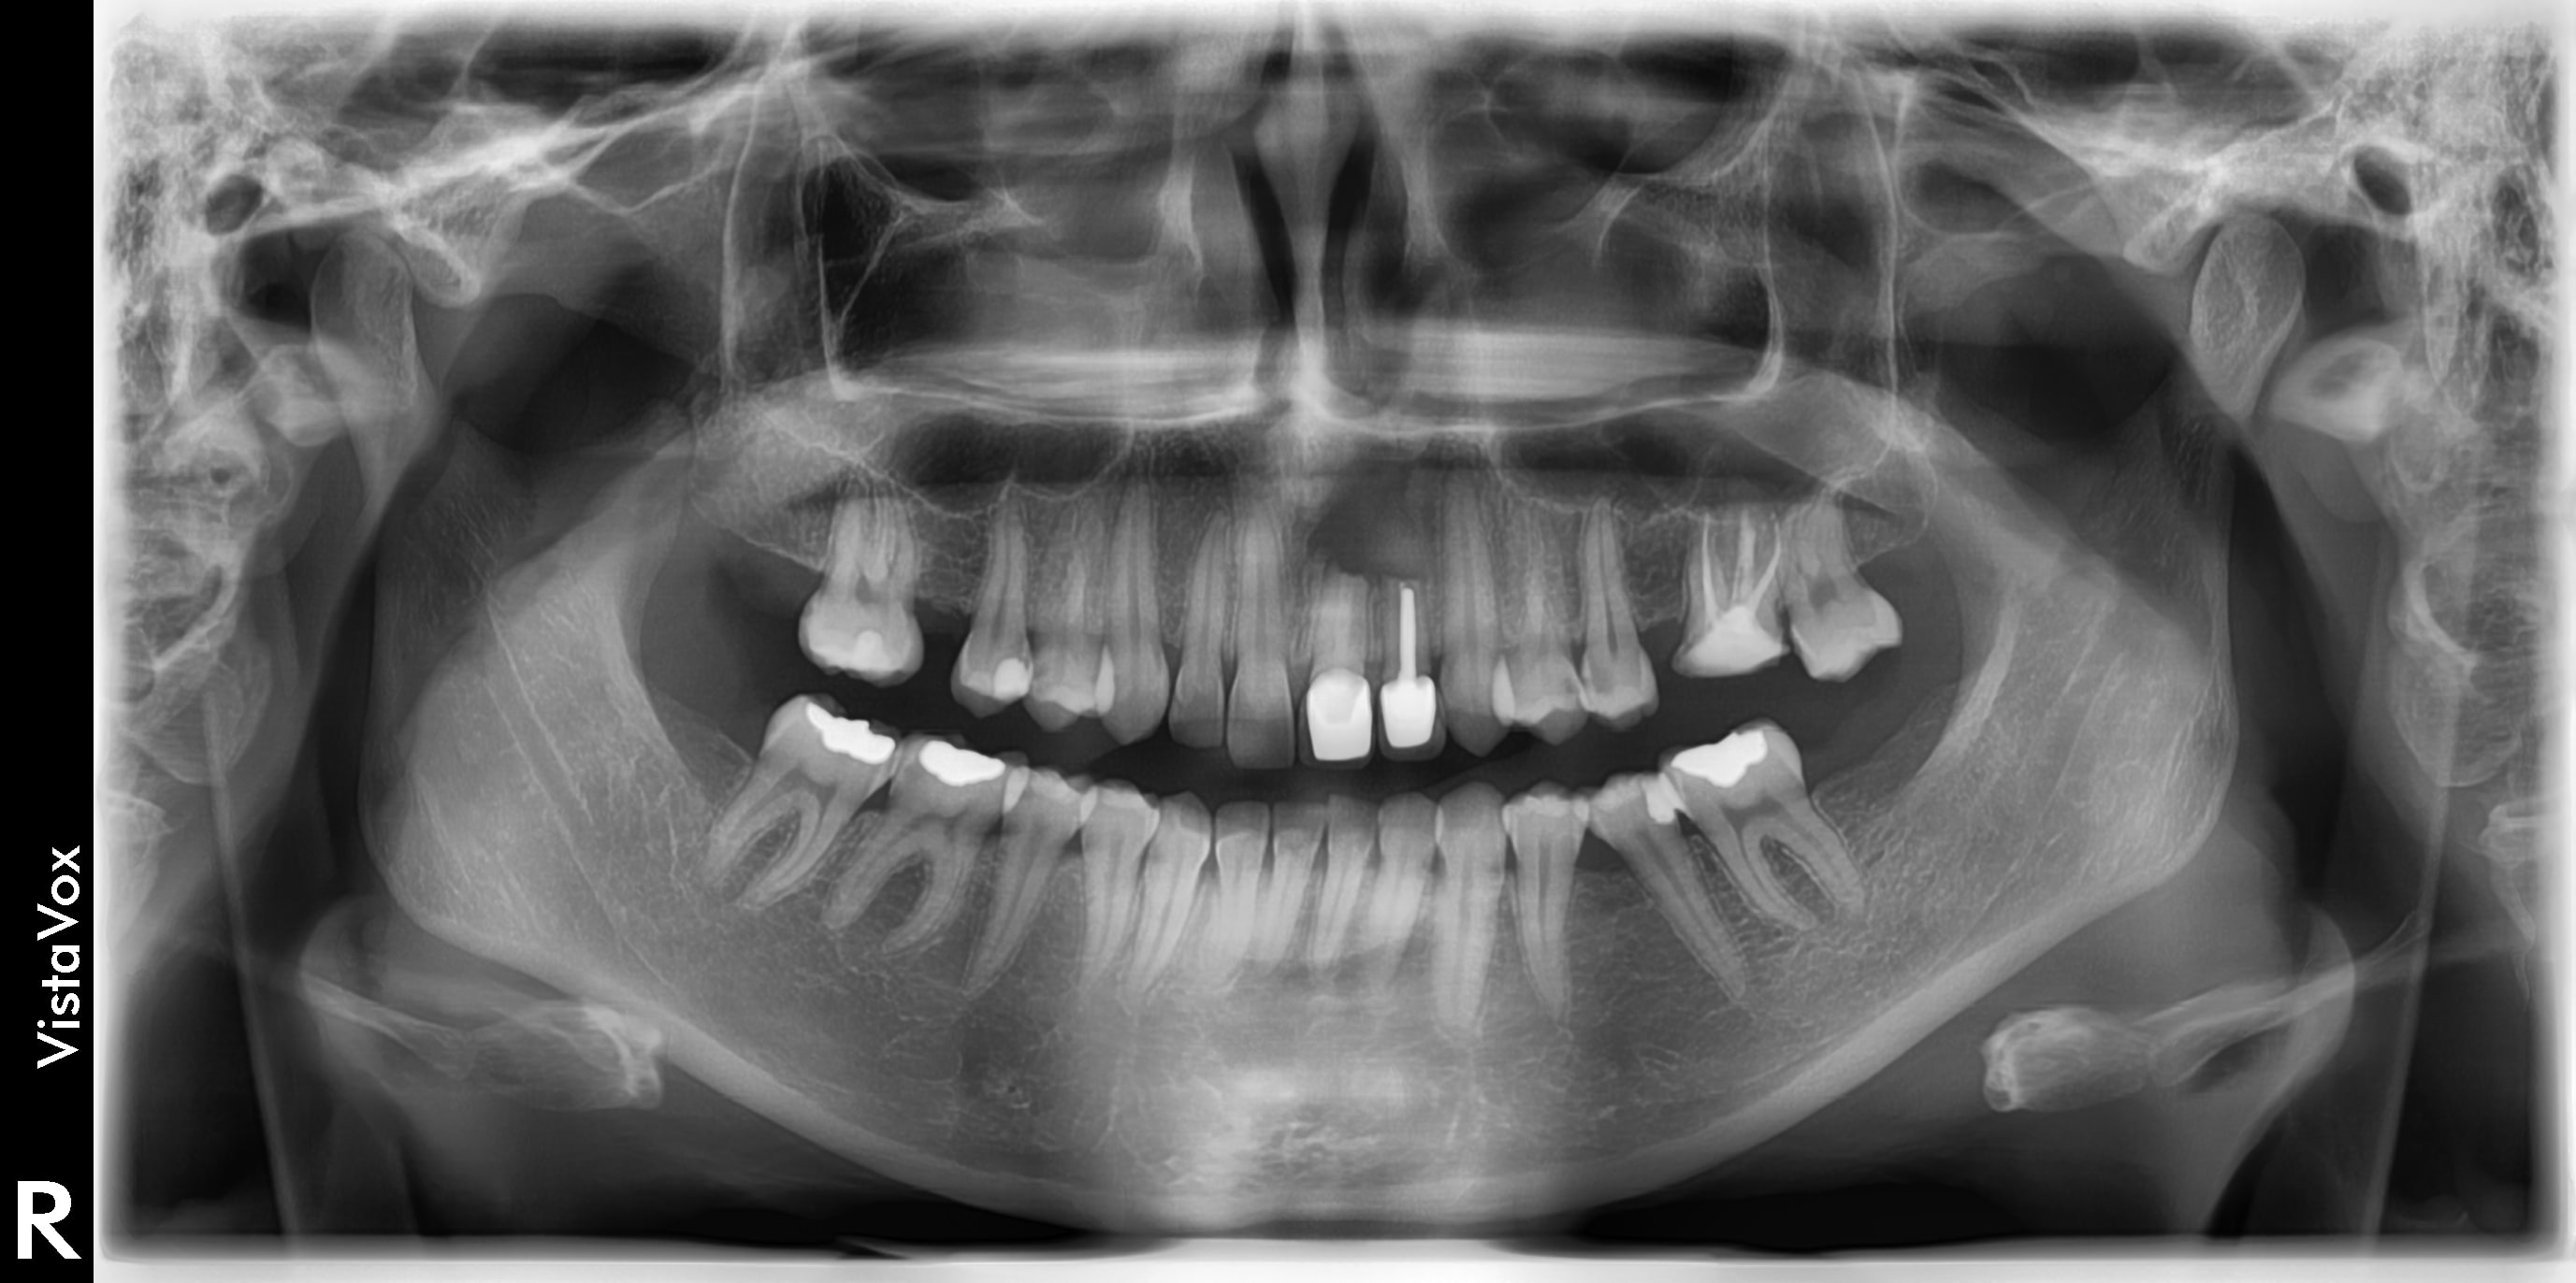

Patiente de 23 ans à peine.

La résection a été faite 1 an plus tôt...

Elle consulte pour remplacer toutes les dents manquantes, réparer toutes celles qui faut réparer, mais surtout pour son sourire qui la complexe à cause de la 21 et 22 (couronne céramo-métallique moche, couleur plus saturée que la 11 et 12, métal visible, coloration violette de la gencive...), grande cicatrice au niveau péri apicale avec fistule et un peu de pus à la pression, absence d'os à laquelle il faudrait remédier...

Pas de douleur. Pas de mobilité.

Elle revient demain, je ferais une rétro et un cone beam.

Je rajoutes quelques coupes et une rétro... C'est vraiment un massacre à la tronçonneuse!